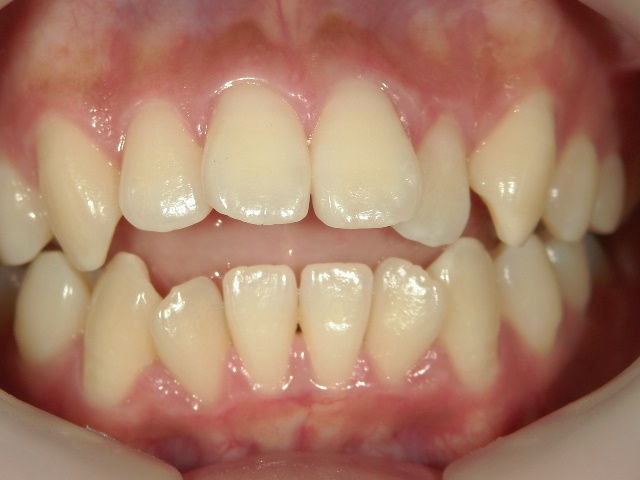

主訴:奥歯で噛んだときに前歯が噛み合わない

高校時代には、歯並びを改善しようと様々な矯正サイトを閲覧し、自分自身が開咬であることを知りました。開咬とは、上下の歯を噛み合わせた時に前歯に隙間ができることを言います。そういえば、麺を前歯で噛みきること、ハンバーガーにガブッと噛みつくことができませんでした。

2年を少し過ぎたころには歯並びが良くなり、開咬もだいぶ改善されました。結婚式を予定していたため早期終了をさせていただきましたが、開咬が治ってハンバーガーをガブッと噛みきることができるようになって、とっても嬉しいです。式でもきれいな歯並びで、思いっきり笑うことができました。

出っ歯や八重歯などの歯並びの悪さばかりが気になっていましたが、開咬には前歯で物が噛みきれない、しゃべるときに息が漏れるなどの症状の他に、奥歯ばかりに負担がかかる為、歯の寿命を縮めてしまう可能性がありました。矯正で改善することができて本当によかっと思います。みなさんも歯並びで気になることがあったら、気軽に相談してみてくださいね。